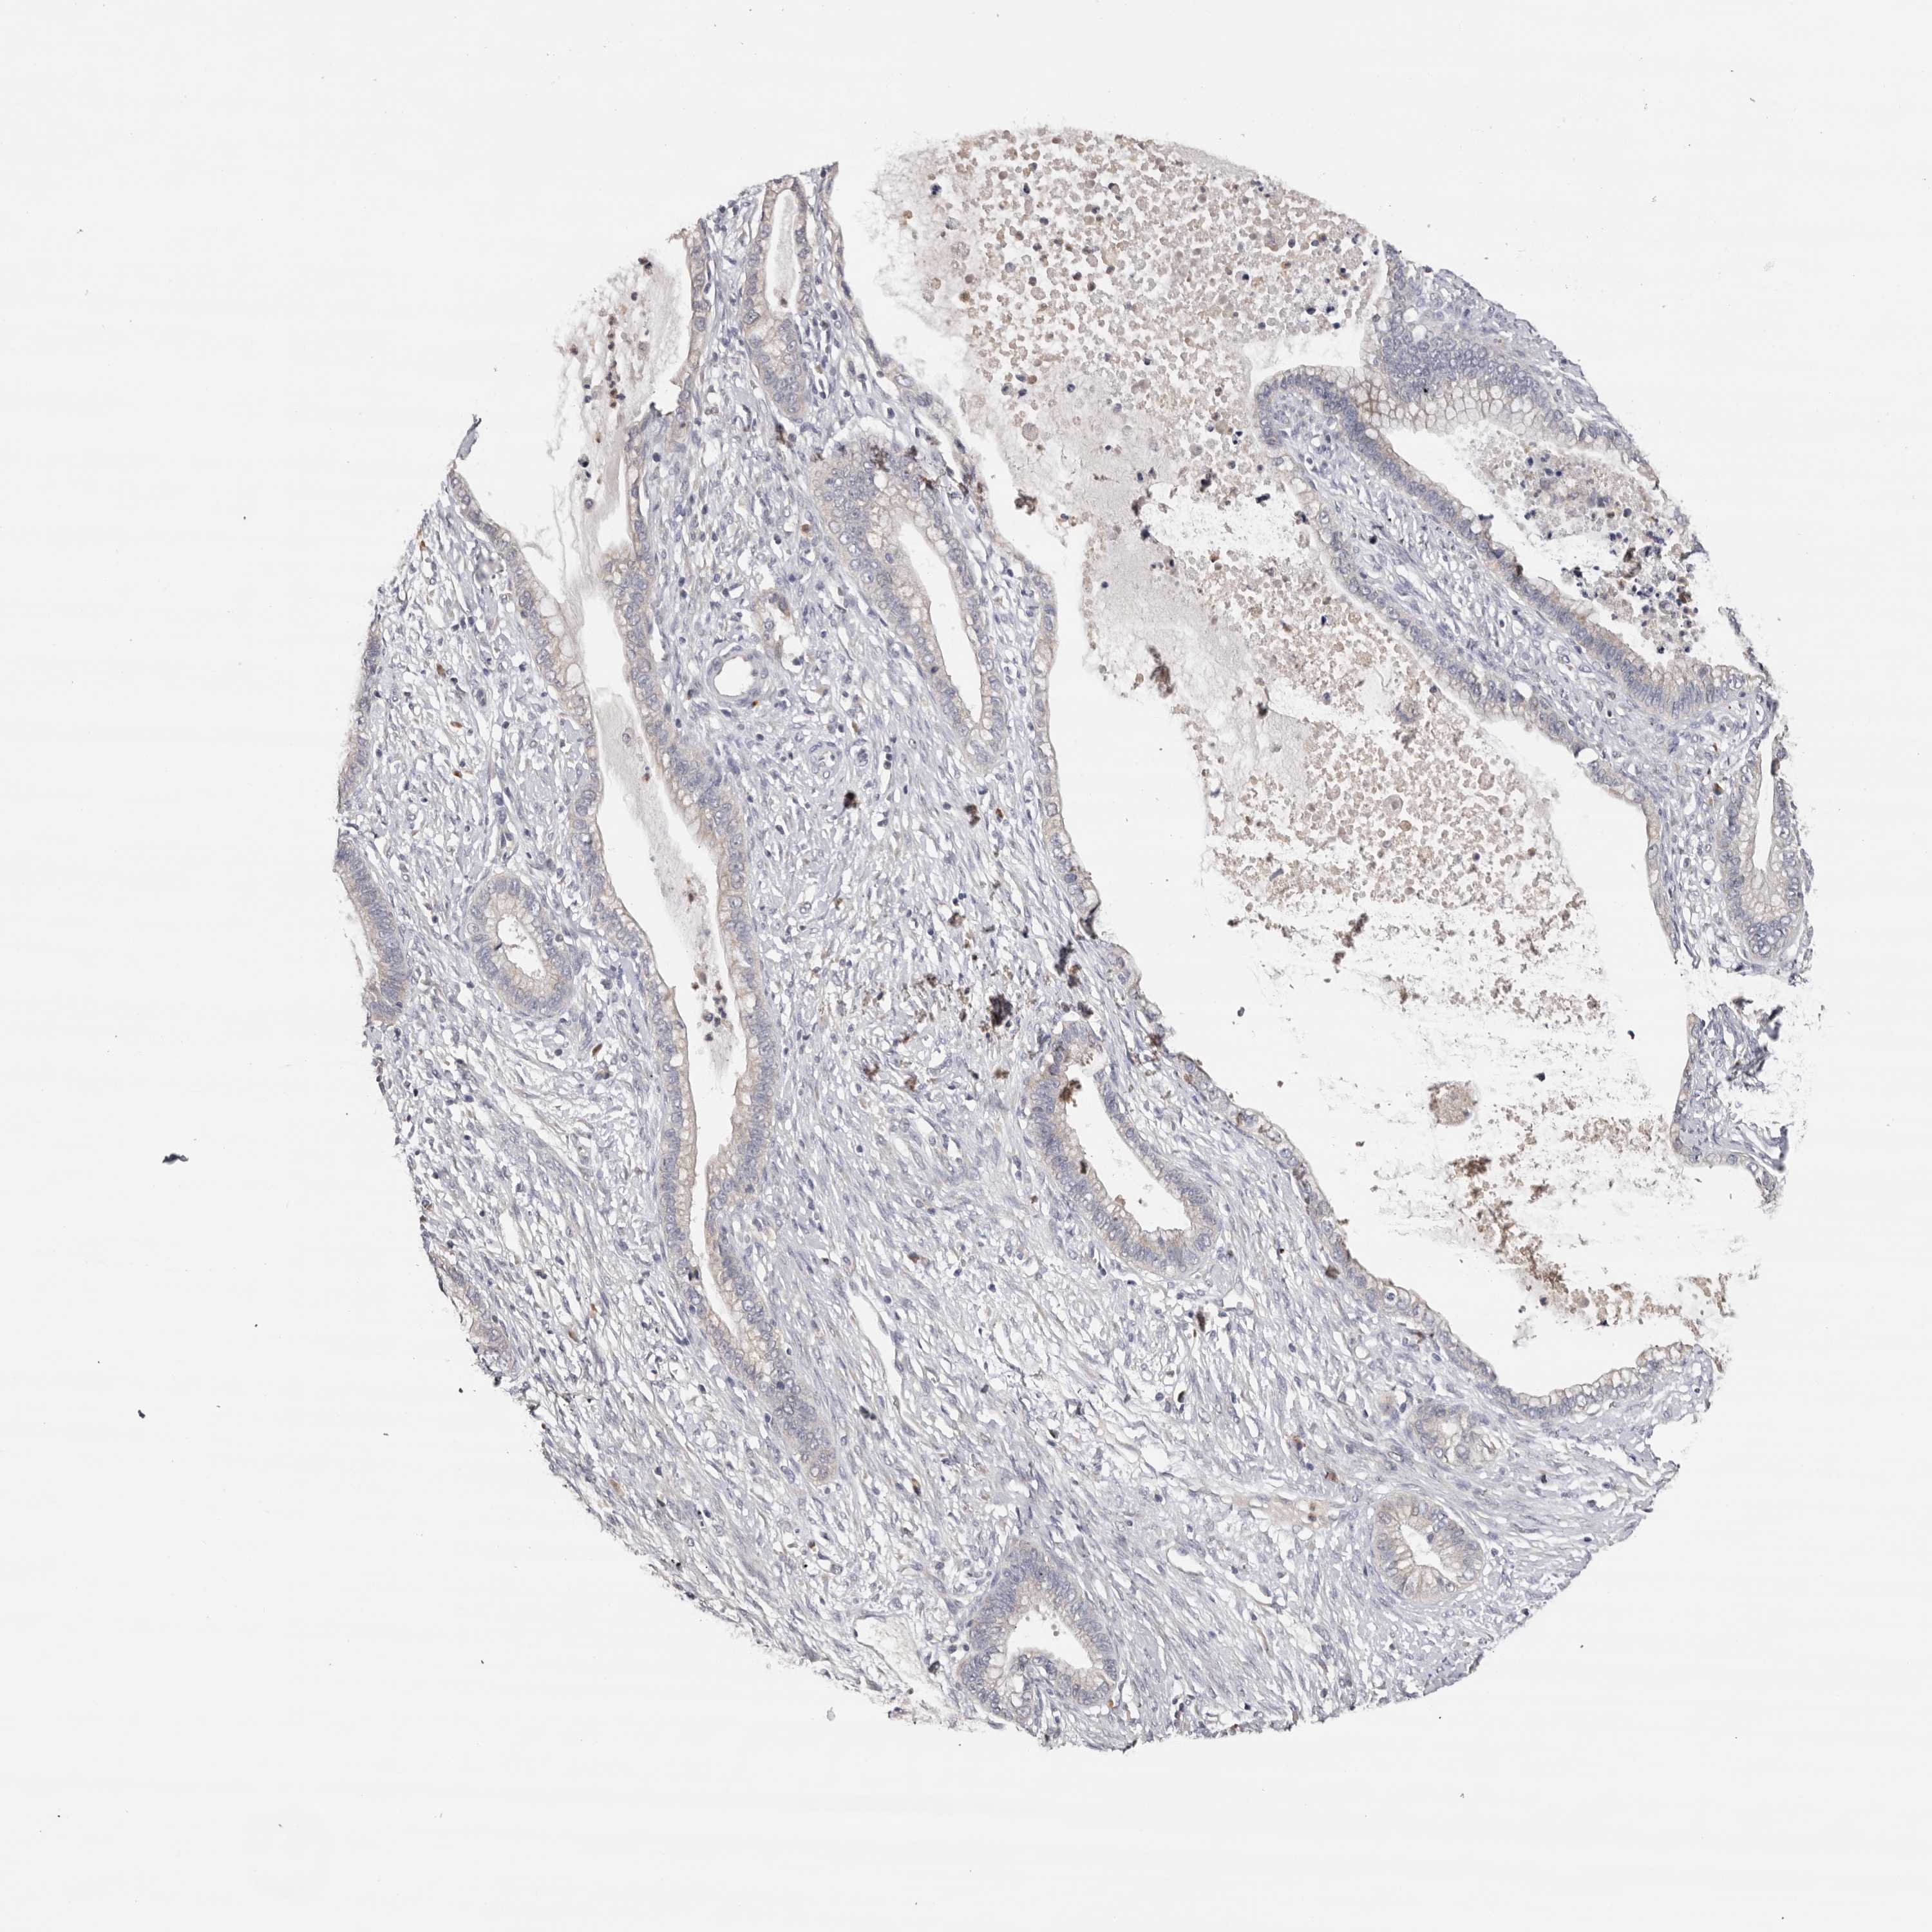

CERVICAL CANCER - Protein expressioni

A mouse-over function shows sample information and annotation data. Click on an image to view it in a full screen mode. Samples can be filtered based on level of antibody staining by selecting one or several of the following categories: high, medium, low and not detected. The assay and annotation is described here.

Note that samples used for immunohistochemistry by the Human Protein Atlas do not correspond to samples in the TCGA dataset.

Antibody stainingi

Antibody staining in the annotated cell types in the current human tissue is reported as not detected, low, medium, or high, based on conventional immunohistochemistry profiling in selected tissues. This score is based on the combination of the staining intensity and fraction of stained cells.

Each image is clickable and will lead to virtual microscopy that enables deeper exploration of all samples and also displays staining intensity scores, fraction scores and subcellular localization as well as patient and tissue information for each sample.

Antibody HPA023081

Antibody HPA023103

Antibody HPA024795

Squamous cell carcinoma, NOS

Adenocarcinoma, NOS